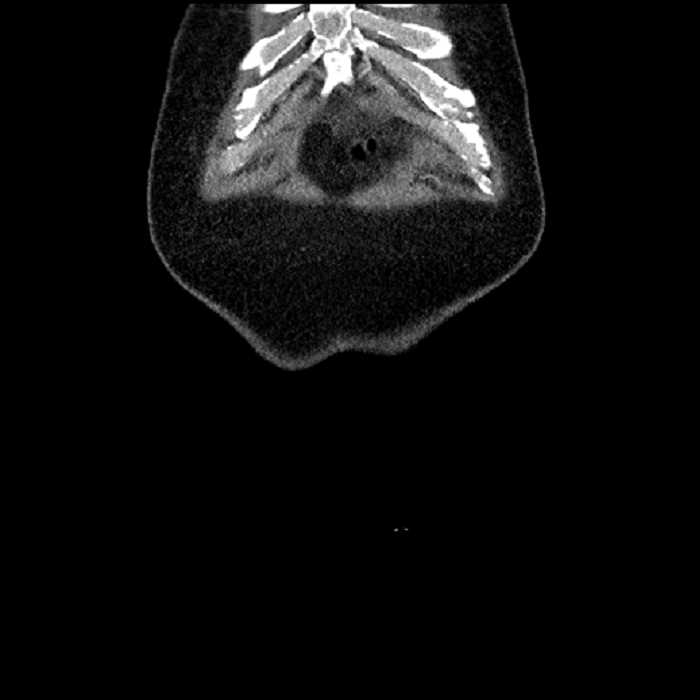

• The classic CT imaging appearance is a double target sign with internal low density surrounded by an internal enhancing rim (capsule) and a low density external rim (edema)

Hepatic abscess showing the double target sign with low density internally surrounded by a thin inner enhancing rim (red arrow) and ill-defined outer low density rim (yellow arrow). Blue arrow indicates an internal septation. Red arrows: additional smaller subcapsular abscesses. Red arrow: focal contained perforation associated with diverticulitis.